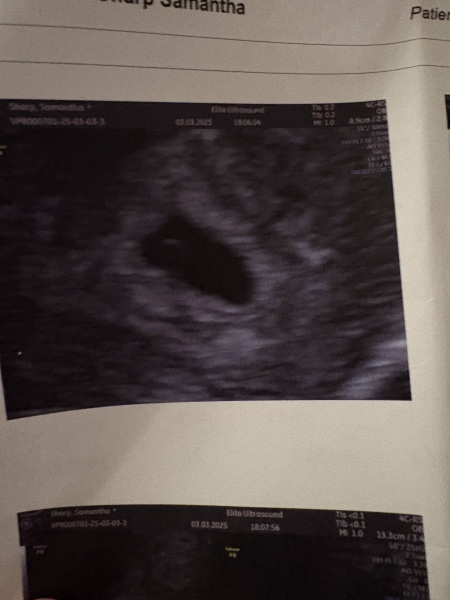

SampT · 03/03/2025 19:25

Looking for some positivity. Found out I was pregnant 20/2. My last menstrual period was 8/1. Had a scan today expecting to be 7+5 and scan only showed GS and Yolk sac. Estimating me to be around 5/6 weeks. Back for a rescan in 7 days. Has this happened to anyone and they’ve maybe ovulated later than expected?